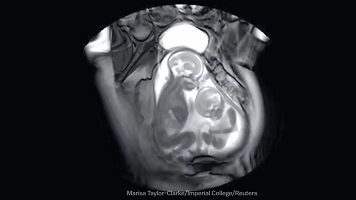

前方高能预警

亲都亲完了这时候就要进入正题了

下面这个图就是啪啪啪的关键过程了

这时候我们的血液流动会重新分配

血液会在短时间内聚集在体表,导致

皮下毛细血管血流更加丰富,这使你的皮肤

表面敏感度和感受比平时更加明显,肌肉开始

从不规律性收缩转向为有规律的收缩